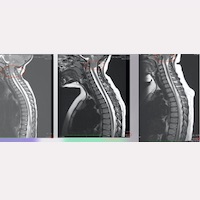

En la casuística de nuestro Instituto, en algún caso este ascenso se observa en 1-2 años, mientras que en otros casos, a lo largo de los primeros 5-10 años postoperatorios (Fig. 1).

El hecho de que mediante una acción quirúrgica indirecta y localizada en otra zona anatómica, se produzca el cambio de la posición de las amígdalas cerebelosas, junto con la mejoría clínica que experimentan los pacientes; para nuestros médicos es una confirmación más de que la causa de la patología se ha eliminado, dejando de ser activa y de traccionar la médula, el tronco encefálico y la columna vertebral.